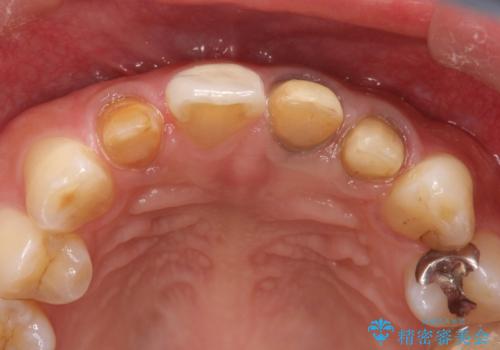

- 全体的なガタガタと前歯をきれいにしたいとのことで来院されました。

下の歯は重度のガタガタがあり、上の前歯は何本かが神経の治療がしてある状態でした。

インビザラインにて歯並びを整え、上顎の前歯にセラミックを装着する計画としました。